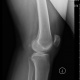

Рентгенологическое исследование: в костях обоих коленных суставов маловыраженные инволютивные изменения; суставные щели нормальной ширины; определяются частичные обызвествления менисков в обоих суставах (рис. 59).

Рис. 59, а, б. Обызвествление полулунных хрящей - менисков в обоих коленных суставах.